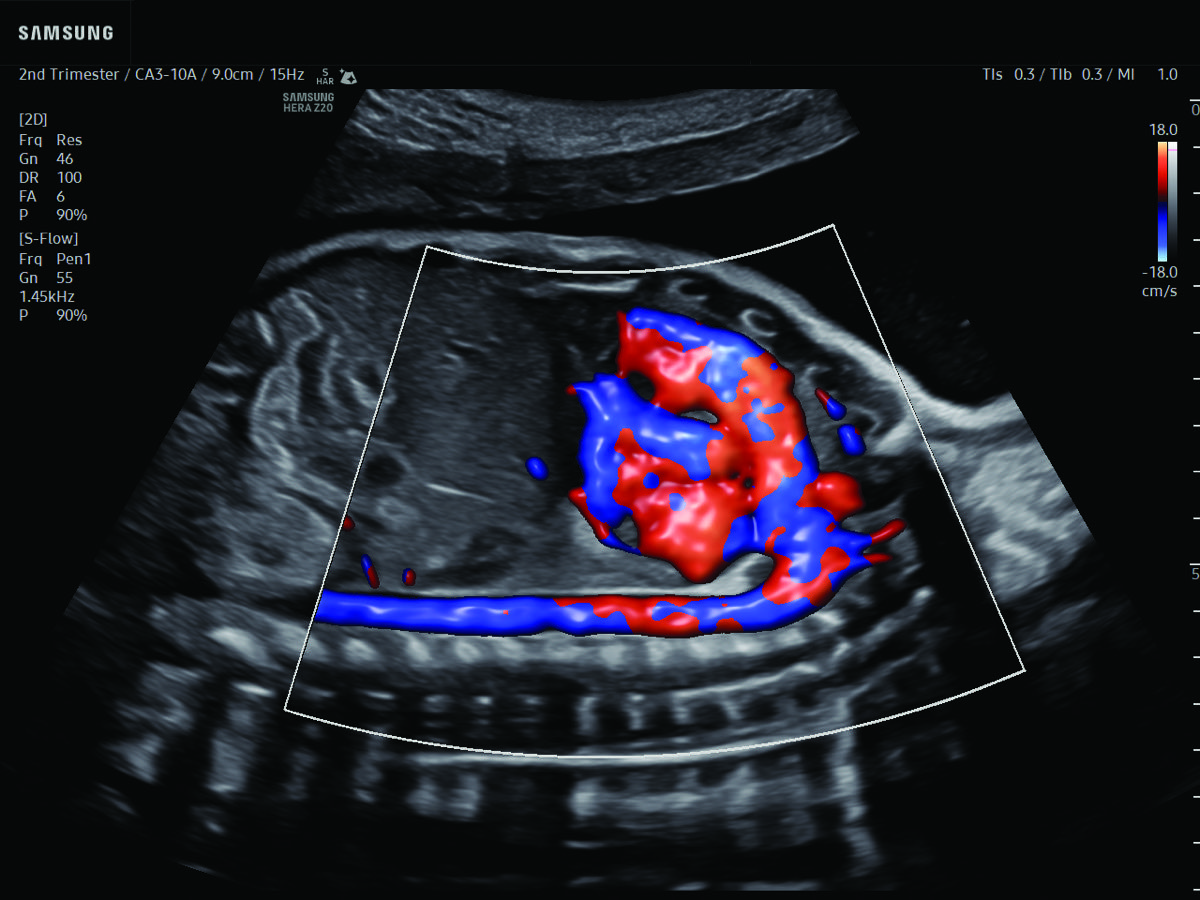

Procedural Services

Comprehensive, advanced and expert MFM care for high-risk pregnancies

- Fetal anomalies